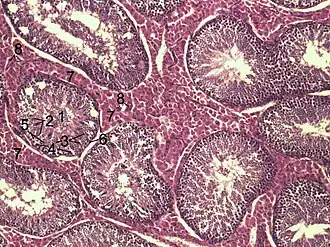

![]() Secção histológica do parênquima testicular de um javali. 1 Lumen of Tubulus seminiferus contortus 2 espermátide 3 espermatócitos 4 espermatogônia 5 célula de Sertoli 6 Célula Mioide 7 Célula de Leydig 8 capilares | |